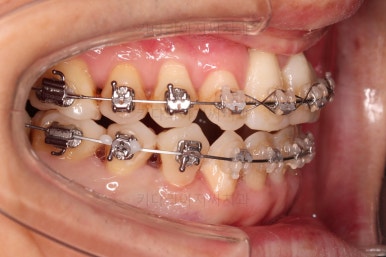

부산구순구개열교정 키다리아저씨치과에 처음 내원하셨을 당시의 입안의 모습입니다.

구순구개열 환자분의 일반적인 입 안의 특징은 다음과 같습니다.

골 결손부위의 치아 결손이 빈번하다.

구개열 봉합술을 어린 나아이에 받기 때문에, 해당 부위의 상흔이 남는다.

상흔의 영향으로(피부 상처도 일반 피부 보다는 상처가 아문 부위가 더 단단하죠.) 입천장의 잇몸이 굉장히 단단하다.

그래서 가로폭의 성장이 잘 되지 못하여 악궁(치아가 배열된 U자 형태)이 협착된 경우가 많다.

공간 부족으로 치열이 매우 삐뚠 경우가 많다.

공간 부족과 악궁 형태 등으로 인해 부정교합이 함께 나타난다.

골 결손부위 근처의 치아는 뼈가 약한 경우가 많아 튼튼하지 못하고 만지면 흔들리는 경우가 많다.

이번 환자분도 이와 같은 일반적인 특징이 그대로 나타나 있었습니다.

양측성 구순구개열이었으므로 작은 앞니(대문니와 송곳니 사이)가 양쪽 다 결손이었고, 또 다른 이유로 아래 앞니도 1개 없는 상태였습니다.

위아래 장치를 부착했습니다.